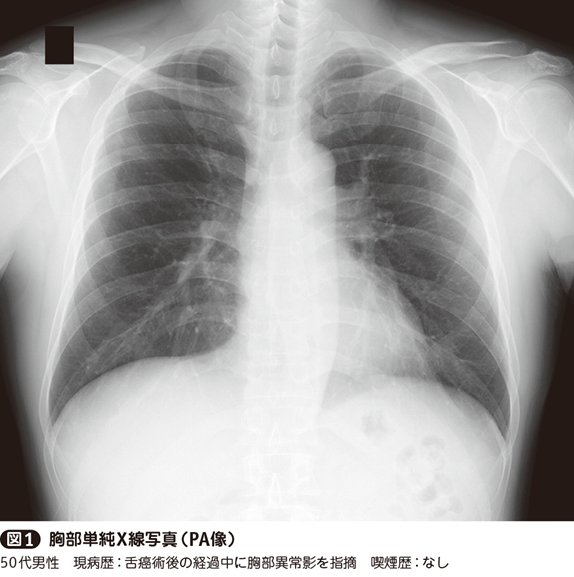

商品詳細ページ | メディカルブックセンター。挑戦本 挑戦本の検索結果 - 通販|セブンネットショッピング。即戦力が身につく 肝胆膵の画像診断(MEDSi社)レビュー|るな(放射線。書店で購入し、一読したため出品します。裁断済み カプラン臨床精神医学テキスト DSM―5診断基準の臨床への展開。神経質な方はご遠慮ください。【裁断済】フローチャートでわかる婦人科外来診療パーフェクトブック。胸部X線画像診断支援ソフトウェア(CXR Finding-i) | コニカミノルタ。中に書き込みはありません。保管に伴う使用感はあります。鼻形成術 = Aesthetic Rhinoplasty : 美容外科手術手技。口腔外科学。防水ビニール→封筒で梱包し佐川急便/日本郵便もしくは佐川急便/日本郵便で発送予定です。「即戦力が身につく胸部の画像診断」芦澤 和人 / 藤本 公則 / 藪内 英剛定価: ¥ 8500#芦澤和人 #芦澤_和人 #藤本公則 #藤本_公則 #藪内英剛 #藪内_英剛 #本 #自然/医療・薬学・健康